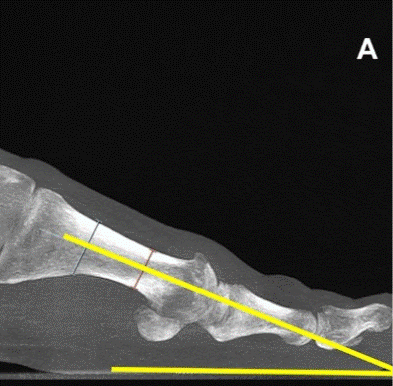

Pie cavo varo y biomecánica del apoyo plantar

Introducción El pie cavo varo es una alteración estructural del pie caracterizada por un arco plantar elevado y una tendencia al apoyo lateral del retropié. Esta configuración modifica de forma significativa la distribución de cargas durante la marcha y la carrera, incrementando el riesgo de sobrecarga mecánica en el borde externo del pie y en […]